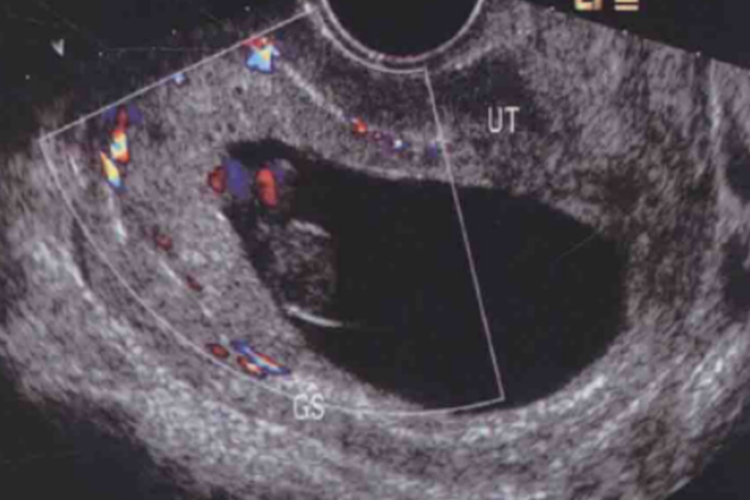

怀孕2个月时胎儿初具人形,头的大小占整个胎体一半,能分辨出眼、耳、鼻、口,四肢已具雏形,B超可见早期心脏形成并有搏动。此时胚胎大小约为2cm,尺寸似葡萄大小。